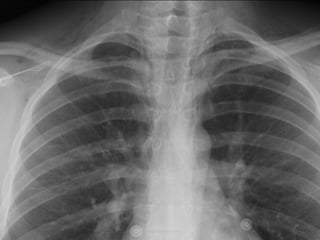

50 y.o femalewith progressive SOB. What can you do to improve SOB?

Volume loss withatelectasis Mass effect with large effusion